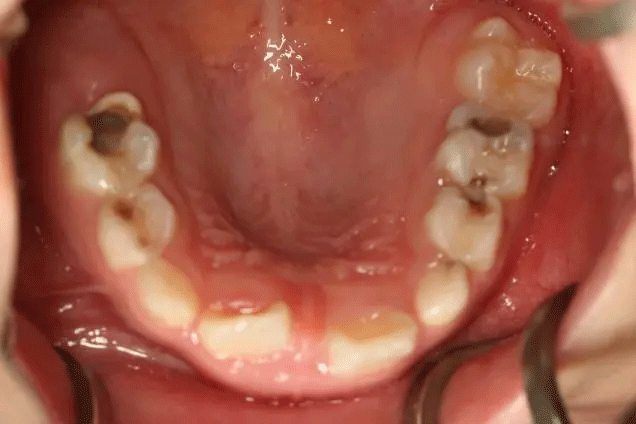

很多家長(zhǎng)對(duì)乳牙蛀牙不以為然

孩子1歲開始已經(jīng)出現(xiàn)齲齒

但是媽媽2年后才帶孩子就診

這時(shí),孩子已經(jīng)斷斷續(xù)續(xù)疼了3年

在門診中發(fā)現(xiàn)

來口腔科檢查的孩子

有些牙齒都已經(jīng)爛得很嚴(yán)重了

甚至牙齒幾乎都爛光僅剩下牙根

孩子不喊疼,家長(zhǎng)很少會(huì)帶來看牙